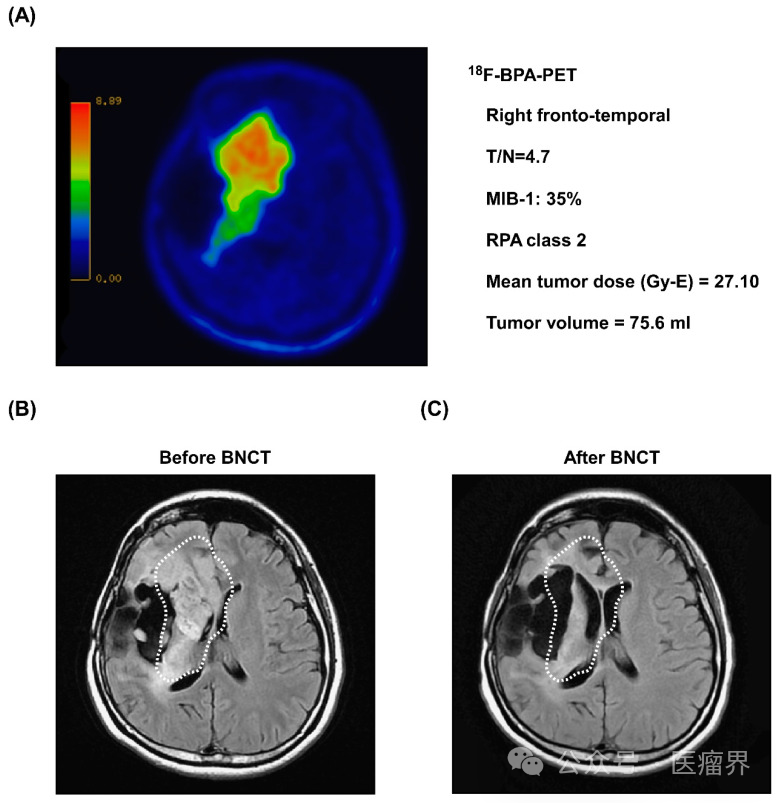

中子治疗即硼中子俘获治疗(Boron Neutron Capture Therapy,简称BNCT)是放射疗法之一。BNCT的原理是利用发生在肿瘤细胞内的核反应摧毁癌细胞。

BNCT(硼中子俘获疗法)是一种先进的放射疗法,其放射束由稳定的硼同位素(10B)与低能热中子反应产生的两束重粒子束组成。

硼中子俘获疗法(BNCT)是一种具有选择性杀伤肿瘤细胞能力的新兴疗法。当硼化合物从颈动脉注入肿瘤细胞时,热中子在核反应堆中照射,硼变成放射性锂,此时发出α射线。α射线的射程极短,因此优先影响肿瘤组织,而保留更多远端正常组织。

硼中子俘获治疗(BNCT)是利用中子和硼的核反应,对正常细胞几乎不造成损伤,是选择性地破坏癌细胞的治疗方法,不仅是初发、单发癌症,还有扩散到个别脏器的癌症、转移性癌症、难治性癌症。

硼中子俘获疗法(BNCT)是一种很有前途的癌症治疗方法,通过选择性地将硼化合物集中在肿瘤细胞中,然后将肿瘤细胞置于超热中子束辐射下,从内部选择性地破坏肿瘤细胞,对健康组织几乎没有损害。